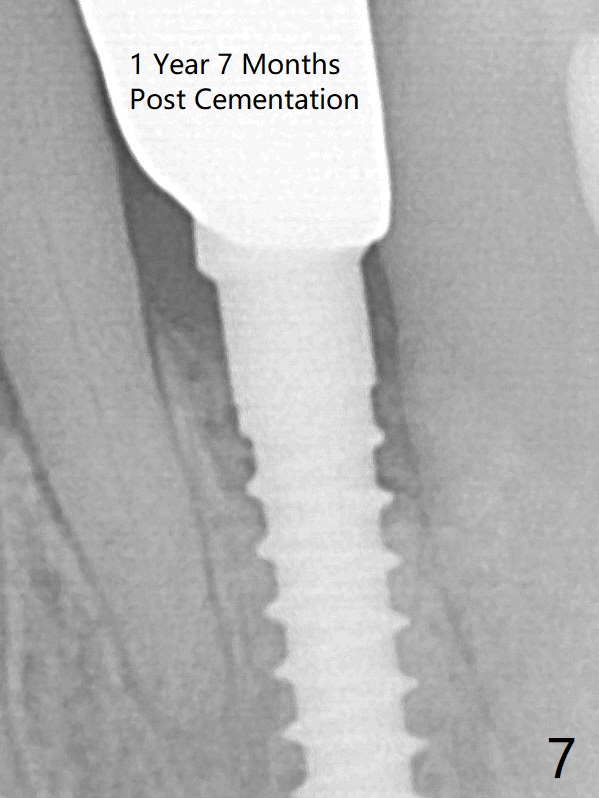

The gingival depth is measured 2-4 mm after extraction. The 1st intraop PA taken with 1.2 mm drill for 16 mm shows the mesiodistal width is 5.11 mm (Fig.2); a 2.5x14(2) mm 1-piece implant is placed with >35 Ncm (Fig.3 with allograft placed). There is no bone loss 3 months postop (Fig.5). The distal crest seems to be reduced in density and lower in height 1 year 7 months (Fig.7) and 1 year 11 months (Fig.8) post cementation. The severity does not worsen probably related to use of water pik.